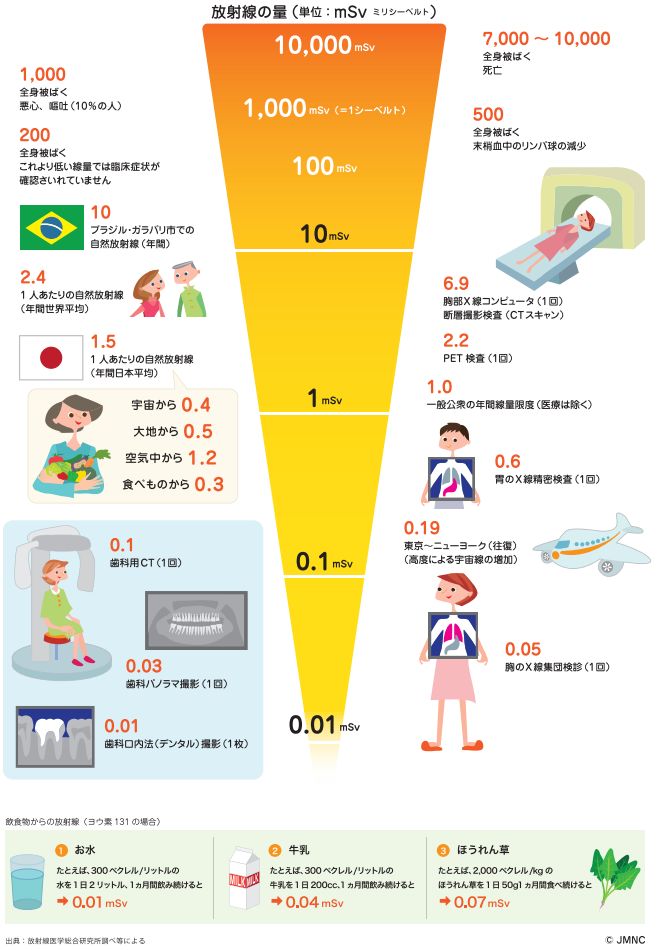

患者様のなかには、X線撮影においての被ばく量を心配される方もいらっしゃると思いますが、日本人一人あたりの自然放射線量は年間1.5mSvと言われている中で、

歯科用X線の被ばく量は、デンタル1枚0.01mSv、パノラマ1回0.03mSv、歯科用CT1回0.1mSvと言われています。これは、胸部や胃のX線検査で浴びる量よりも少ない値です。

一般的な放射線被ばく量についてはこちら